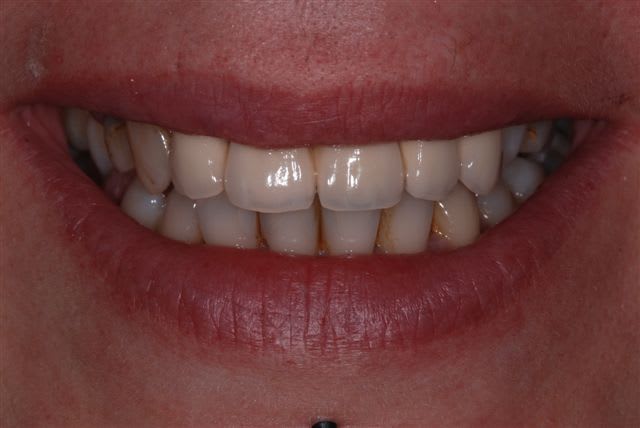

Allez petit quizz, photos de 2 emax ce matin avec un Canon 450D objectif sigma 105mm f20/250.

Quelle différence entre les deux photos?

En fait la différence viens de l'orientation des sources lumineuses. En les gardant à droite et à gauche de l'objectif on à un forte signature du flash sur les reliefs verticaux de la dent (il y a plus de relief et on accentue le phénomène en mettant des réglages d'intensité différents) alors qu'en orientant les sources en haut et en bas, on a moins de signature (c'est mieux pour un relevé de teinte) mais aussi moins de relief.

Conclusion, dans les cas d'esthétique je prend toujours plusieurs clichés avec différents réglages et différentes orientations et on garde le meilleur, il suffit juste de choisir mais là je pense qu'on ne garderait pas tous le même...